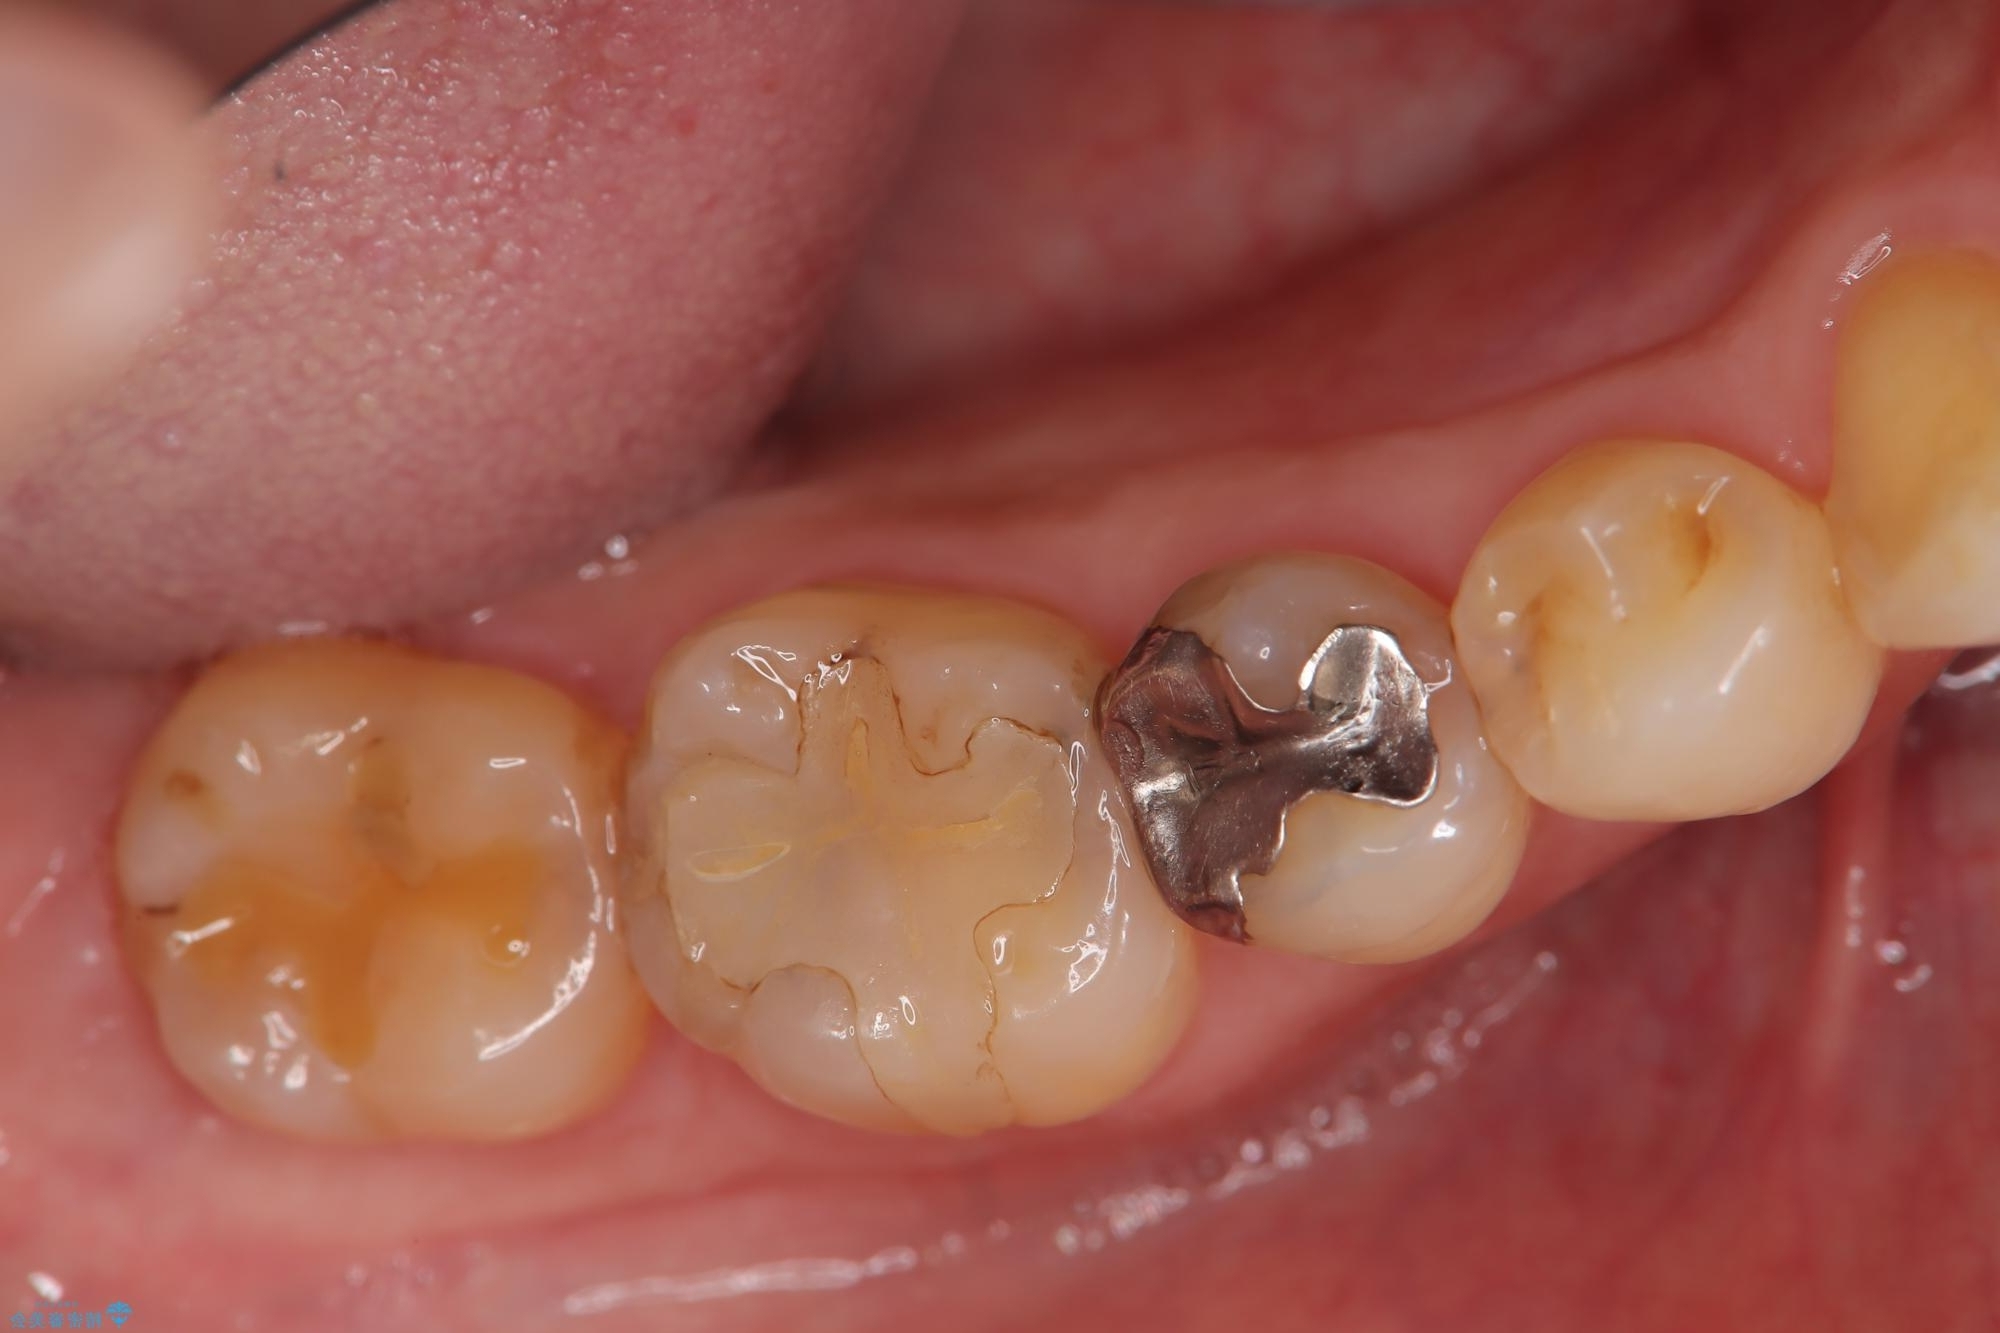

レントゲン検査の結果、古い金属の詰め物の内部に二次的な虫歯が見つかりました。

この虫歯を完全に除去した後、その日のうちに精密なセラミックインレーに替える治療を行いました。術後の経過も良好です。